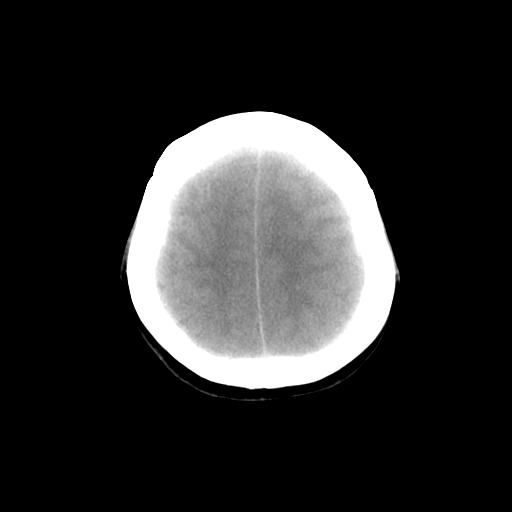

标题: CT14513:女性41岁,头部不适二月余,其它病史不详。请分析 [打印本页]

标题: CT14513:女性41岁,头部不适二月余,其它病史不详。请分析

1.考虑:左侧颞顶叶星形细胞瘤。2.大脑镰下疝。

支持!但楼主所提示处颅骨明显受压变薄,是否有合并蛛网膜囊肿或局部硬膜下水瘤的可能?脑穿通畸形暂不予以考虑:明显占位表现;病侧脑室无扩张;病灶不是较明确的脑脊液密度;边界不清晰。还是mri检查吧,提供的有价值信息更多一些,至少可以排除或肯定蛛网膜囊肿或局部硬膜下水瘤的存在。

1)考虑左侧颞顶叶胶质瘤。2)左侧颞顶部慢性硬膜下血肿?3)大脑镰下疝。